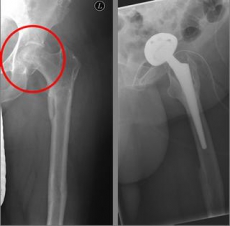

Picture: In this case, there was already a wear of the hip joint and the affected patient was relatively young, so that a cement-free total endoprosthesis (TEP) of the hip was selected for the treatment of the femoral neck fracture. Here, in addition to the femoral head, the acetabular cup was replaced by an implant.

Pertrochanteric fractures, which are not femoral neck fractures close to the hip, are treated with a so-called gamma nail. The rupture here runs through the large and / or small "hillock" (trochanter major and minor) of the thighbone. Here, due to the location of the fracture, the blood supply to the femoral head is NOT compromised. After the operation, an immediate mobilization can take place under pain-adapted full load.

Picture: In this pertrochanteric femur fracture, a gamma nail was used to stabilize the fracture. The femoral head does not have to be replaced in this case, because the femoral neck is intact and the femoral head is still well supplied with blood.